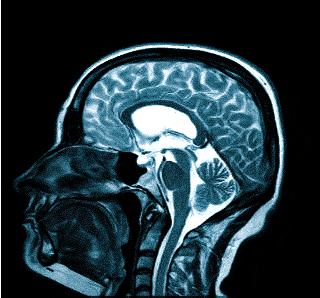

Если при диагностике назначается проведение МРТ головного мозга, то это нужно сделать с целью проверки патологий сосудов.

Мигрень происходит по той причине, что сосуды в мозге человека сокращаются в определенный момент.

За счет этого в головном мозге случается спазм. Томограф данного типа позволяет узнать о нарушениях кровотока, а также отражения различного ишемического типа.

В любом случае различные обследования должны иметь полный характер. Это позволит врачу увидеть всю картину заболевания и назначить максимальное точное лечение. За счет полной диагностики получится узнать причину боли в голове. Как правило, специалисты в первую очередь делают МРТ мозга.

Обязательно. Головные боли связаны с разными причинами. МРТ головного мозга позволяет исключить самые опасные из них – опухоли, поражение сосудов (аневризмы, мальформации и т.д.), «водянку» мозга (гидроцефалия) и т.д. Часто головные боли связаны с воспалением в придаточных пазухах носа, что также хорошо видно при МРТ. Если при МРТ не нашли патологии мозга, это очень хорошо. Разумеется, обследование даёт информацию о патологиях, но не всегда даёт ответ на вопрос «почему болит голова?». Головные боли имеют сложное происхождение. Ваш невролог будет подбирать лекарство, которое вам обязательно поможет.

Головные боли одна из наиболее частых жалоб, с которой обращаются пациенты к невропатологам, а также для углубленного обследования. Известно много причин головных болей, среди которых можно выделить «органические», то есть те которые можно увидеть, и функциональные. К «органическим» причинам головных болей можно отнести опухоли, гидроцефалию («водянку», избыточное количество жидкости в головном мозге), патологию сосудов (аневризмы, мальформации, спазмы, кровоизлияния), воспаления придаточных пазух носа (синуситы), воспалительные процессы мозга и его оболочек (церебрит, энцефалит) и некоторые врожденные аномалии мозга. Зачастую причину головных болей непосредственно увидеть невозможно. Тогда причину головных болей можно искать по косвенным признакам. Так, остеохондроз шейного отдела позвоночника вызывает напряжение мышц шеи и затылочной области, что обозначается как «боли напряжения», напряжение глазодвигательных мышц также часто вызывает боли в глазах и голове.